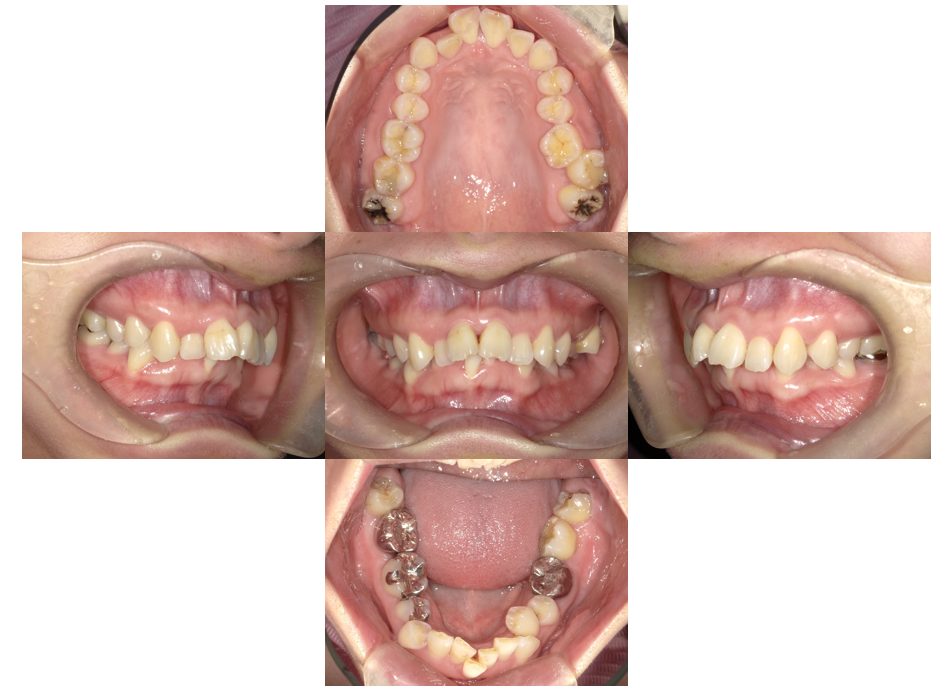

| 主訴 | 過去作成した右下の被せ物がずれて入っており、たまに腫れる。歯並びも気になる。 |

| 治療内容 | 矯正治療を行いました。 |

| 治療費 | 800,000円(税込み) |

| 治療期間 | 2年半(矯正治療期間 2年) |

| 治療回数 | 30回 |

| 想定されたリスク | 術前に基礎資料を整え分析し、セットアップモデル等でシミュレーションをしておかないと、予定通りの治療が行えないリスクがあった。 |